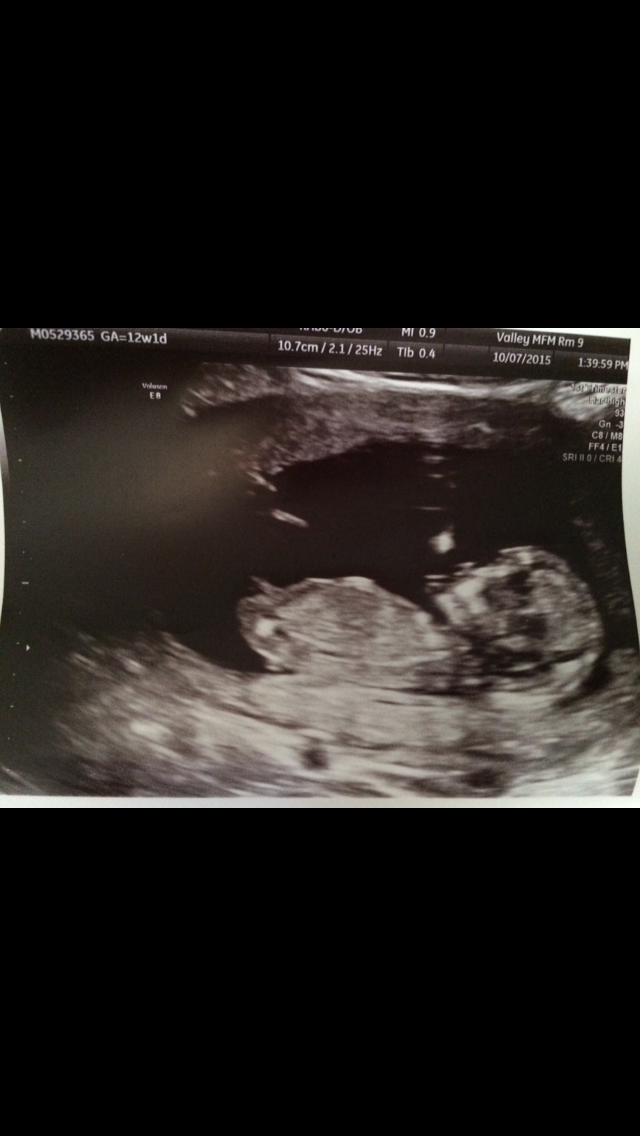

Had my 12 week 2 day sonogram yesterday! Baby is healthy and was moving all over the place, but since he/she was literally doing a headstand they had a hard time getting the measurement, so I have to get another one next week!